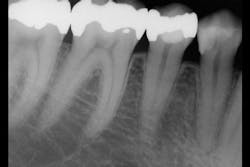

Observe Figures 4 and 5 for the following discussion:

The first molar has a painful, cracked distolingual cusp and lingual caries. Should the amalgam restoration be removed and another intracoronal restoration placed? I see this procedure routinely suggested by some clinicians who promote bonding of the remaining tooth structure to the subsequent direct or indirect restoration. My long-term clinical experience and in vitro research at Clinicians Report Foundation refute that recommendation. Such restorations are only a fraction as strong as a virgin tooth, and I strongly suggest that this procedure eventually results in a doomed restoration and tooth. When more than one-half of the cusp-tip to cusp-tip tooth structure is removed, the tooth has minimal strength remaining and a full-crown or onlay covering all of the remaining cusps is indicated.

Observe the second premolar. It has a deep base in it, but only minimal removal of tooth structure in the isthmus area. If this amalgam were to be replaced with another restoration, what would be appropriate?

- An intracoronal resin-based composite restoration would provide acceptable strength, assuming proper acid-etching of the remaining enamel walls is accomplished. Our in vitro research estimates that such a restoration is about 60% as strong as a virgin tooth.

- Is amalgam indicated? Apparently many dentists believe it is. A recent Clinicians Report Foundation survey of thousands of mostly North American dentists showed that 60% of them were placing amalgam up to 10% of the time. Personally, I have not placed an amalgam for many years and find that the following procedure satisfies the intracoronal restoration need for such a tooth. If the box form is deep, place resin-modified glass ionomer, such as 3M Ketac Nano, GC Fuji II LC, or Riva Light Cure HV (high viscosity) in the apical one-third of the box form, cure it, and place composite for the remainder of the restoration.

- How about an indirect inlay in this tooth? My clinical experience says no. Having placed many inlays and onlays on such teeth over several decades, there is no question as to which type of restoration fails most. Many of the inlays fail within a few years, while the onlays have far fewer failures. Should one cusp be left standing, bonded to an indirect restoration? Our research shows the restoration with a cusp standing alone is significantly weaker than a virgin tooth.

- What about an onlay on this tooth? If both cusps are covered with an onlay material such as IPS e.max, the strength has been shown scientifically to be greater than a virgin tooth. If cusps are left standing alone, the strength is far less than a virgin tooth. Except in rare cases, do not leave cusps standing alone, even though many clinicians promote this concept. If you want longevity for the restoration, cover the cusps.

- Is a crown indicated? For some of you who do not place onlays, a crown is a good choice. However, an onlay preserves the facial and lingual surfaces of the tooth, along with the original color of the tooth. Learn to do onlays. They can by beautiful, conservative restorations.

- In my opinion, if the second premolar restoration needed to be replaced, a well-placed resin-based composite would serve this patient for many years.

Now, observe the second molar. It is still serving well with a 20-year old amalgam in it. If it required replacement for some reason, the same rationale as described for the second premolar is acceptable. However, unless the patient does not desire to remove the amalgam, leave it for another many years. If the patient is concerned about the alleged challenges with amalgam, provide information about the amalgam controversy and let the patient be involved in the decision. The international research on large amalgam restorations shows about twice the longevity of composite in such sized restorations.